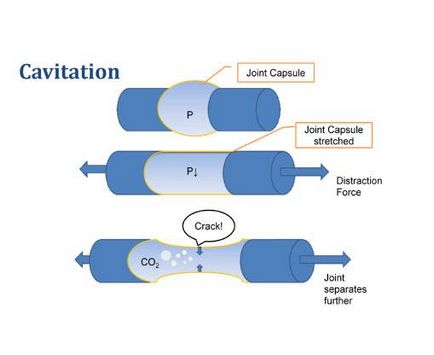

Abban az időben, amikor az érintkező felületek közötti csontok ízületi eltűnik, ízületi folyadék nyomás leesik, és a gázt tartalmazza feloldva szabadul vezikulumokban, mint buborékok megjelennek nyitott palackokban szénsavas vizet. Hipotézis magyarázza a megjelenése a válság ujjait a közös gázbuborék tolta tovább, 1947-ben két orvos a Szent Thomas' Hospital, London, aki végzett kísérletekben röntgengép.

Tanulmányok kimutatták, hogy az ízületi folyadék tartalmaz sok oldott gáz - a szén-dioxid (körülbelül 15% -a). 1947-ben godu Wheeler Haines javasolt (az ellenőrzés révén kapott X-ray), amely miatt előfordul, hogy egy éles klikk üregképződés gáz, ami megteremti a lehetőséget a hirtelen kiterjesztése mozgástartományt, és generál hangot.

Azonban a nagy sebességű kamera, kimutatták, hogy a vezikulumok ismét esett le egy 0,01 másodperc után előfordulása. Később sokáig úgy gondolták, hogy spadenie gázbuborékok hatására közös összeroppant. Mivel nem minden a gázbuborékok összeomlása, időre van szükség annak teljes feloldódás (körülbelül 15 perc) az ízületi folyadékban, mint a szükséges időt ízületi felszínek közelebb (csak kavitációs hatás).

Például, meghúzásával vákuum ujját metacarpophalangealis közös, a gáz üregbe hirtelen, amelyeket azután azonnal lehullott, és amely generálja rezgést, amely átmegy a környező szöveteket. Sőt kiderült, hogy a hang képződése okozza, és nem spadenie buborékok!

Minden esetben, az összeroppant és az „eltérés” közös társított gyors megjelenését gázzal telt üregek keletkeznek, a buborék a szinoviális folyadékban - rendkívül csúszós anyag, amely nedvesíti ízületek. Amikor egy közös felület hirtelen „eltér” folyékonnyá válik ahhoz, hogy töltse ki a térfogatát közös, így az üreg jön létre, és ez vezet a kialakulásához hang.